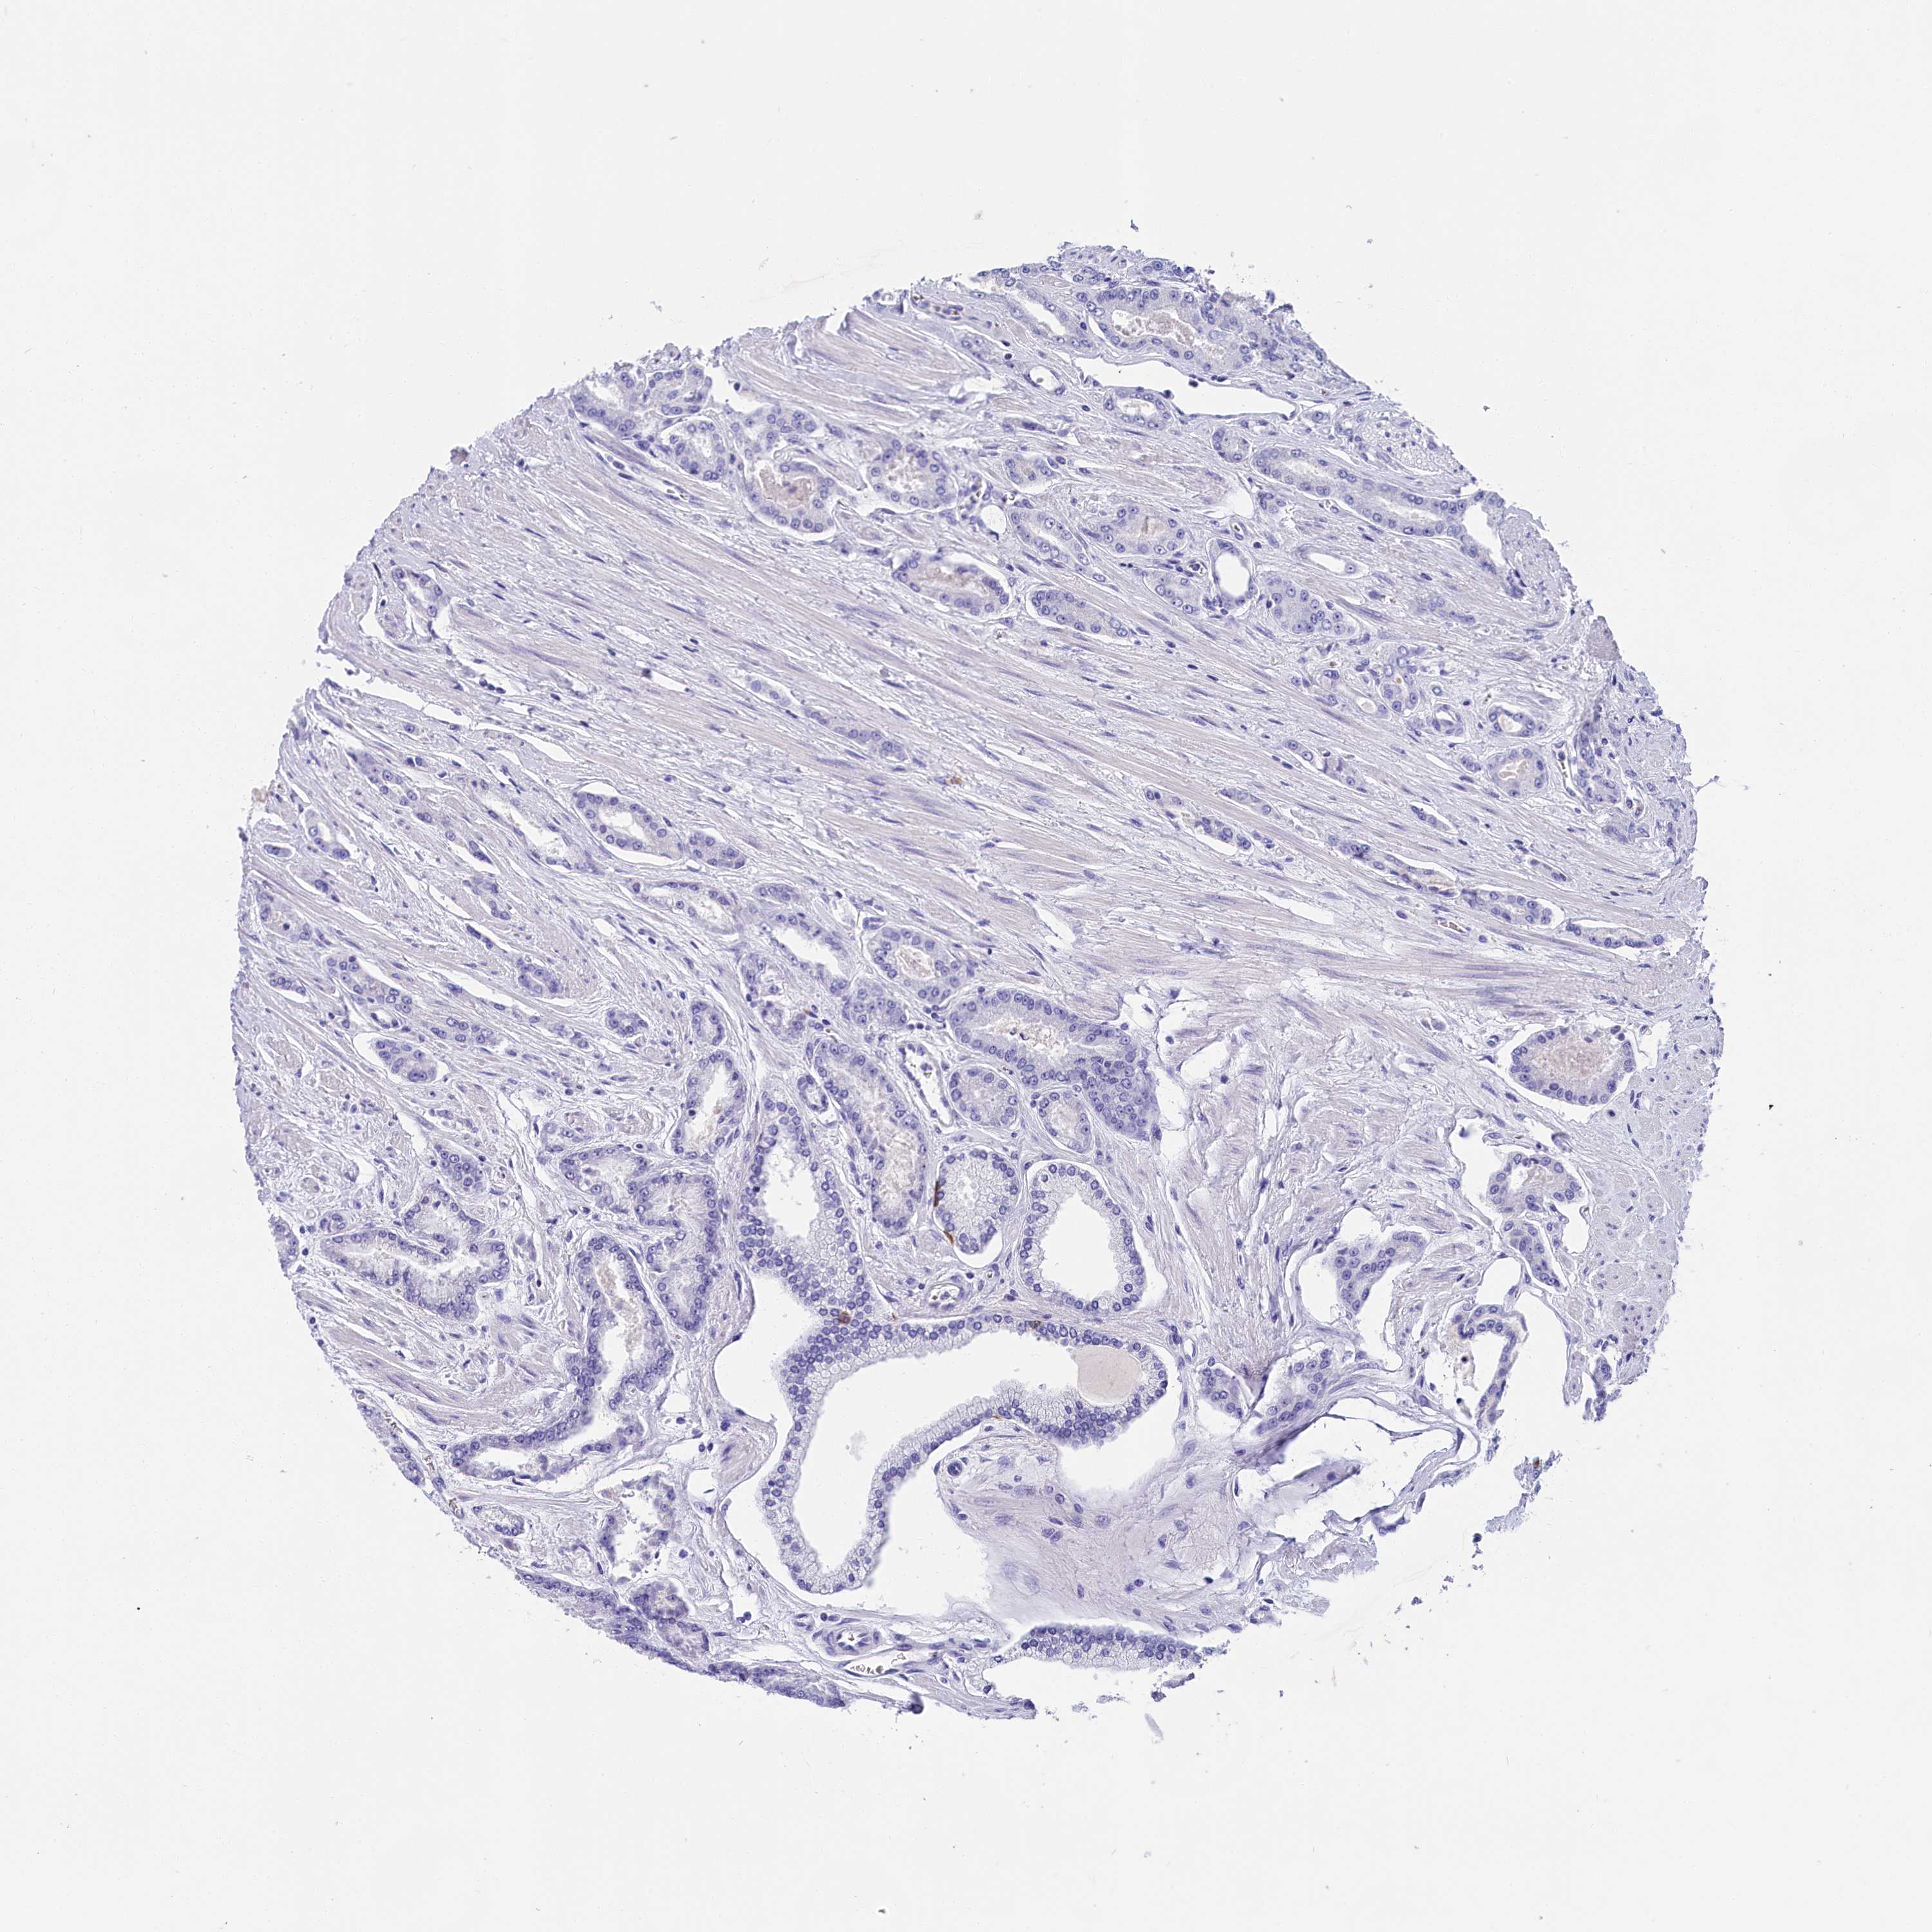

PROSTATE CANCER - Protein expressioni

A mouse-over function shows sample information and annotation data. Click on an image to view it in a full screen mode. Samples can be filtered based on level of antibody staining by selecting one or several of the following categories: high, medium, low and not detected. The assay and annotation is described here.

Antibody stainingi

Antibody staining in the annotated cell types in the current human tissue is reported as not detected, low, medium, or high, based on conventional immunohistochemistry profiling in selected tissues. This score is based on the combination of the staining intensity and fraction of stained cells.

Each image is clickable and will lead to virtual microscopy that enables deeper exploration of all samples and also displays staining intensity scores, fraction scores and subcellular localization as well as patient and tissue information for each sample.

Antibody HPA041487

Antibody HPA063633

Antibody CAB018755

Staining

High

Medium

Low

Not detected

Intensity

Strong

Moderate

Weak

Negative

Quantity

>75%

75%-25%

<25%

None

Location

Nuclear

Cytoplasmic/membranous

Cytoplasmic/membranous,nuclear

Adenocarcinoma, NOS

Adenocarcinoma, High grade

Adenocarcinoma, Low grade